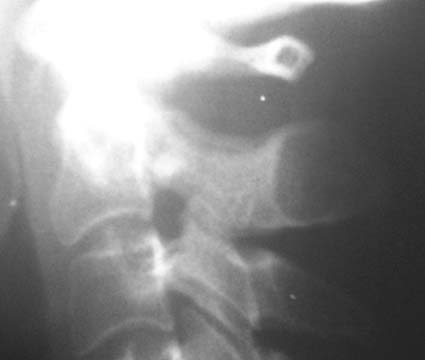

女,45岁,近来感颈部疼痛,头晕,夜不能寐,按之枢椎棘突,感有硬结感,疼痛,骨科怀疑骨囊肿,拟手术,请大家帮忙看一下,是否是正常的?

楼主所指的枢椎棘突密度减低区属正常表现,你可能多拿几个颈椎侧位片看看。

下面是我刚从网上下载的几张颈椎图片。